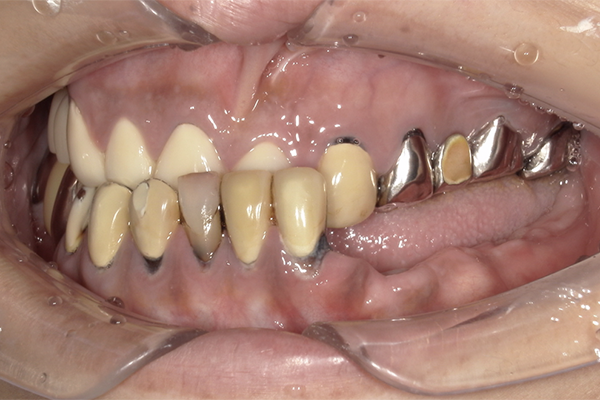

| 主訴 | 全体的にきれいにしたい |

|---|---|

| 治療内容 | 午前中に上下顎共に重度の歯周病、虫歯のため全ての歯を抜歯させていただき下顎はインプラントの土台を3本埋入し歯型を取り午後に上部構造(下顎全ての歯)を装着、上顎は一度総入れ歯を装着させていただきました。 治療が1日で完了しその日のうちに噛めるようになります。 |

| 治療期間 | 2回(1回目に資料取りをさせていただき2回目に下記の全ての治療をさせていただきました。) |

| 治療費 | 250万円 |

| 治療 リスク | 抜歯した部位などに関しては当日痛みが出ますので痛み止めなどを処方させていただきます |